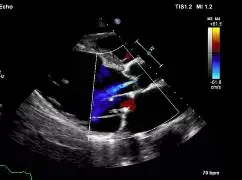

An echocardiogram is a non-invasive ultrasound test that provides detailed images of the heart’s structure and function. It plays a central role in the diagnosis and monitoring of a wide range of cardiac conditions, including valvular heart disease, cardiomyopathies, heart failure, and congenital abnormalities. Echocardiography also assists in evaluating symptoms such as shortness of breath, chest pain, palpitations, and fatigue.

At Prime Cardiology, we use high-quality echocardiography system with advanced imaging capabilities, including 3D echocardiography and myocardial strain analysis. These tools enable more precise assessment of cardiac function and early detection of subtle abnormalities, supporting accurate diagnosis and tailored management.